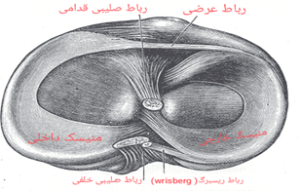

قبل از اینکه به بررسی اختلالات منیسک زانو بپردازیم ، یک بررسی کلی از ساختار منیسک و نقش آن در مفصل زانو داشته باشیم.

منیسک ساختاری غضروف مانند (به بافت غضروف شبیه اما به مراتب از آن محکم تر می باشند)از جنس فیبری غضروفی (فیبروکارتیلاژ) در زانو است که به مفصل زانو ثبات می بخشد و منیسک زانو به عنوان ضربه گیر عمل می کند و از استخوان ها در برابر سایش و پارگی محافظت می کند. هر یک از زانوهای شما دارای دو تکه از این ساختارغضروف مانند است که بین کندیل های استخوان فمور ( ران ) و تیبیا ( درشت نی در ساق پا ) مانند بالشتک (بدلیل خاصیت ارتجاعی) قرار گرفته است :

- منیسک داخلی در قسمت داخلی زانو قرار دارد. (به شکل سی C لاتین)

- منیسک جانبی در قسمت بیرونی زانو قرار دارد. (به شکل او O لاتین)

- ظاهر مینیسک ها در مقطع زانو مثلثی شکل بوده .

- تغذیه منیسک در قسمت مرکزی ازطریق انتشار و در قسمتهای محیطی آن از طریق عروق خونی می باشد.

نقش آنها بیشتر کاهش فشارهای وارده به زانو در خلال نیروهای فشاری در حین ایستادن و یا فعالیت های مختلف روزانه می باشد. پس بنابراین کاهش اصطکاک , کاهش نیروهای وارده به مفصل و تعدیل آنها و همچنین افزایش تطابق مفصلی در خلال حرکت ها را مدیون عملکرد منیسک ها در زانو هستیم .

علاوه بر این موارد گفته شده توزیع وزن ، به وسیله منیسک ها انجام می شود . بنابراین اگر منیسک ها وجود نداشته باشند؛ هر وزنی که به استخوان ران وارد شود روی یک نقطه از استخوان درشت نی منتقل می شود و استخوان ران در اثر وارد شدن کوچکترین ضربه ای دچار شکستگی می شود. نقش دیگر منیسک ها در زانو جلوگیری از لغزش رو به جلو استخوان ران است که همین عامل کمک زیادی به رباط های زانو می کند. همچنین منیسک ها نقش مهمی در تغذیه غضروف های استخوان ران و ساق پا دارد و در حقیقت همانند یک اسفنج آغشته به مایع، عامل انتقال مایع سینوویال بر روی غضروف ها می شود.